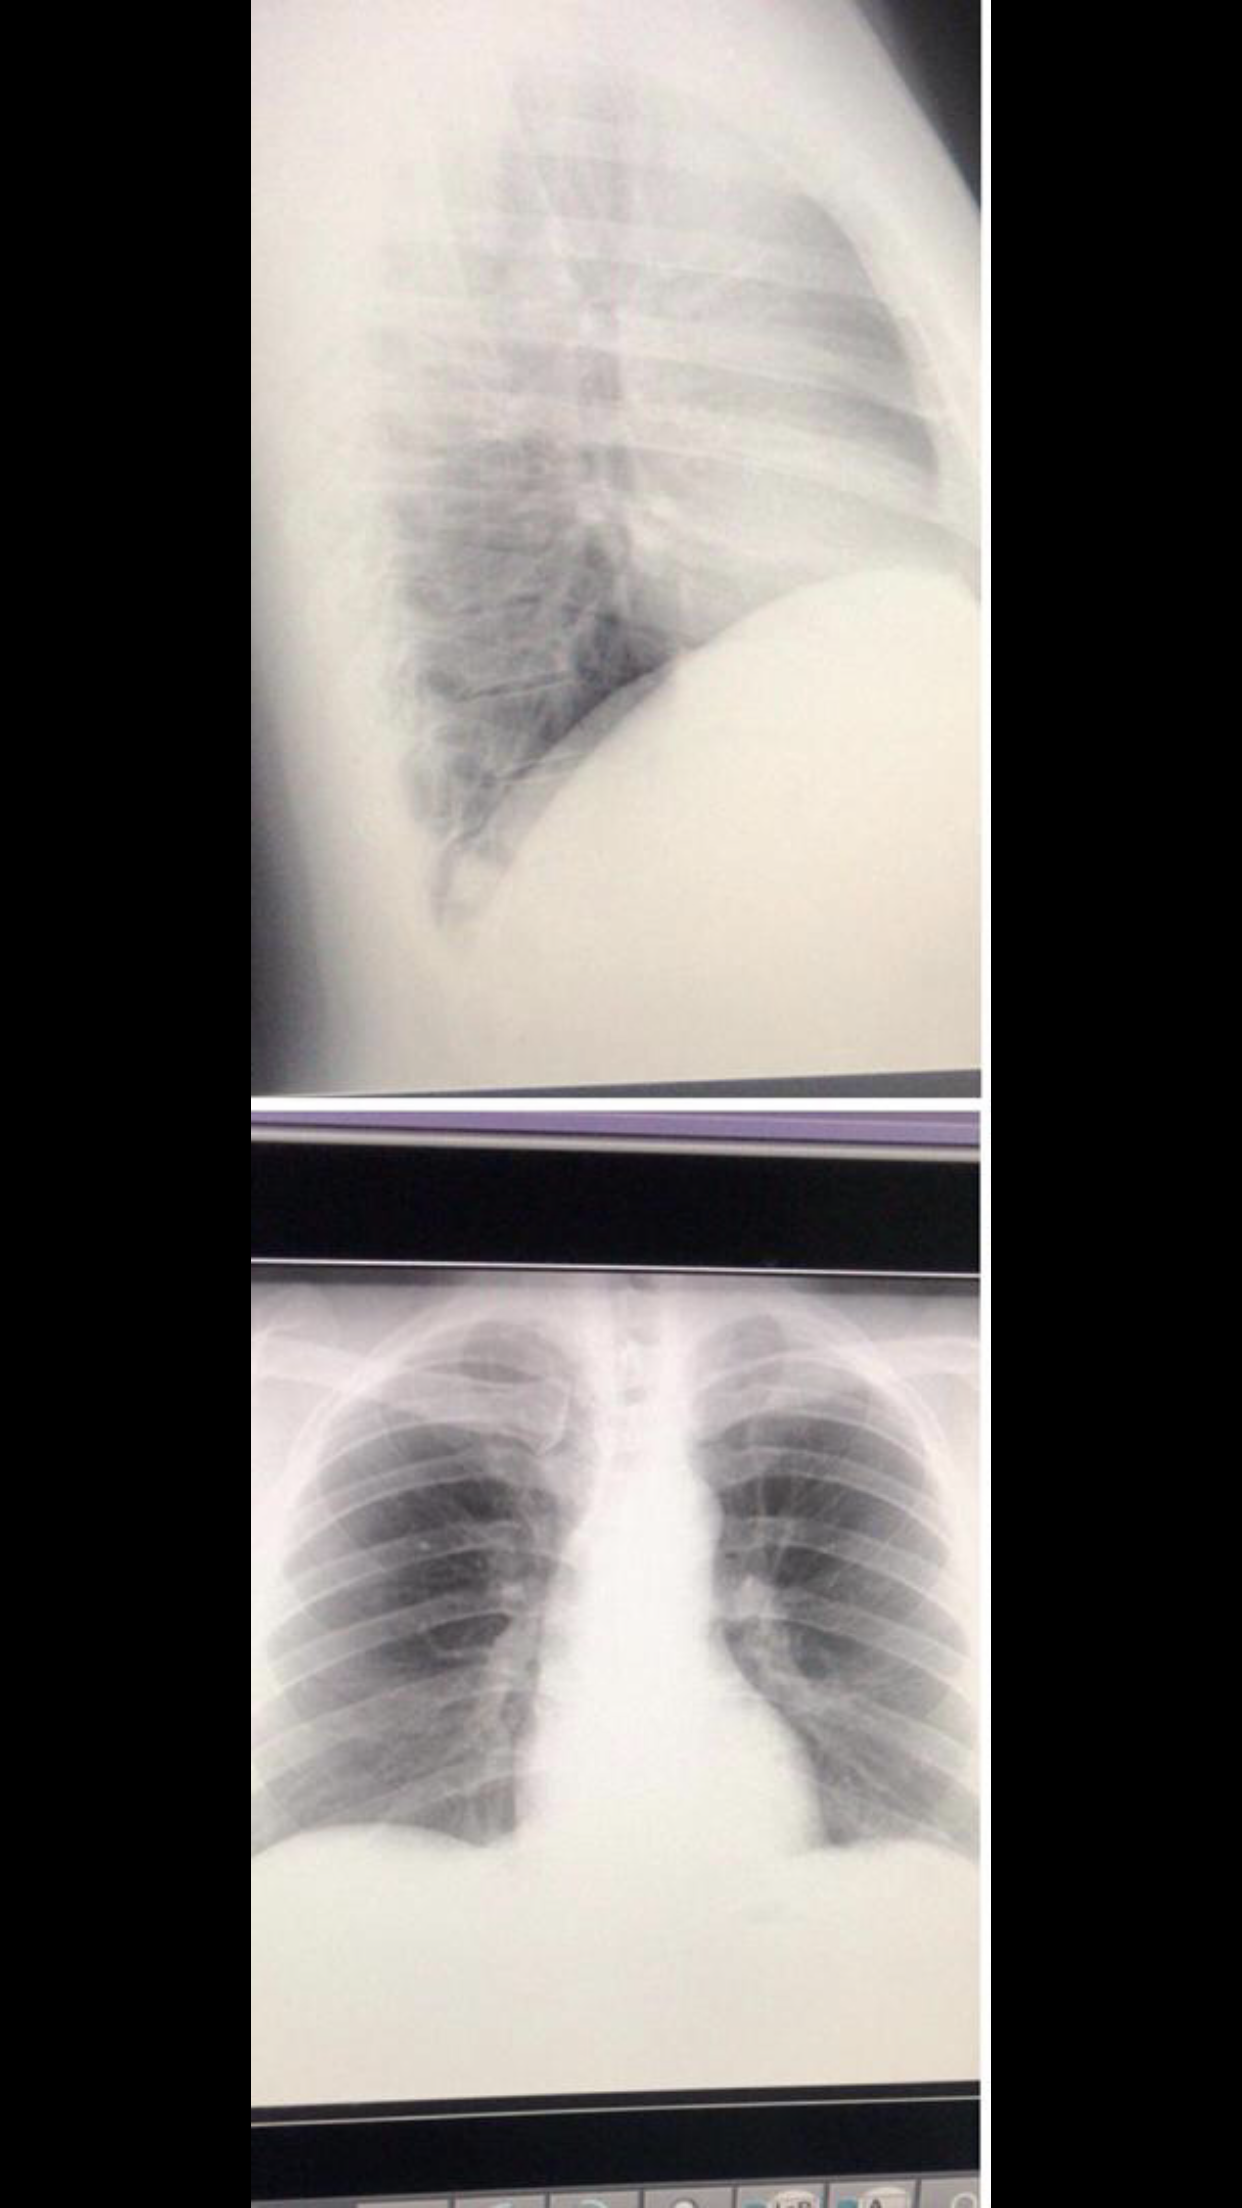

Empiezo el día sintiéndome muy cansado, con síntomas de fiebre, malestar leve y dudando si sería una gripe por mojarme días anteriores o covid, decido ponerme doble tapabocas irme a trabajar con distancia entre las personas!. Pasando las horas decido irme a mi casa porque los síntomas eran mayores, pero antes paso por una clínica para hacerme un rayos X de tórax, para mi sorpresa este fue el resultado:

El daño ya estaba hecho. Decido tratarme en casa por los síntomas que me dieran solo con acetaminofen, grave error.

Me Levantaron para ir a la consulta con el médico neumonologo y como pude fui con mis rayos X, llegamos a la consulta, esperamos una hora sentados en las escaleras para no estar cerca de personas, cuando toco mi turno, el doctor toma mi saturación estaba en 92, tenia tos, el corazón acelerado ( y vaya que no les he contado… soy hipertenso algo grave en esta enfermedad ) y el malestar cada vez peor, el doctor me manda acetaminofen, un anticoagulante en pastillas, dexametazona intectado por 10’dias intramuscular y ya!. A la casa muy normal, me quede inconforme con esto pero la verdad no tenía fuerzas de nada, iba en el carro desmayado de lo mal que me sentía.

De izquierda a derecha mi mejoría